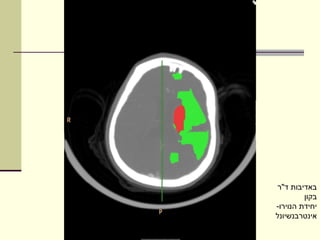

‫באדיבות ד"ר‬

‫בקון‬

‫יחידת הנוירו-‬

‫אינטרבנשיונל‬

‫מתי מטפלים?‬